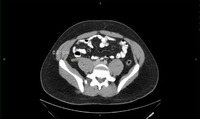

Aneurisma da aorta abdominal: tomografia computadorizada (TC) de um aneurisma da aorta abdominal roto

University of Michigan, mais especificamente os casos do Dr. Upchurch, representando os Departamentos de Cirurgia vascular e Radiologia